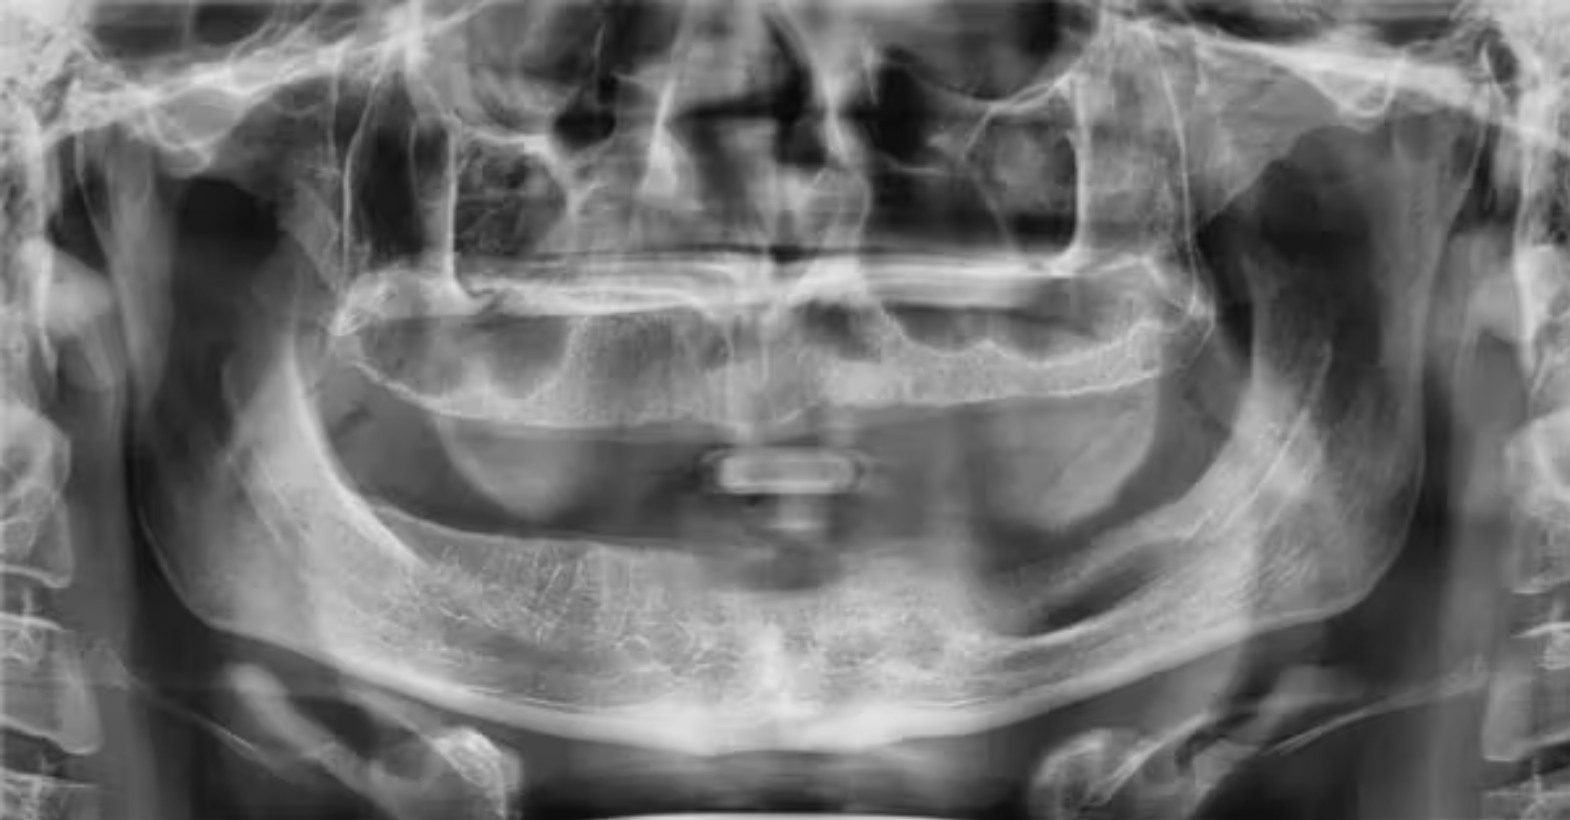

(Hình 3: Mất xương mạn tính vùng răng 31. Sau nhổ răng 32, vùng xương này không bao giờ được tái tạo – Nguồn: Carol Perkins, RDH.)